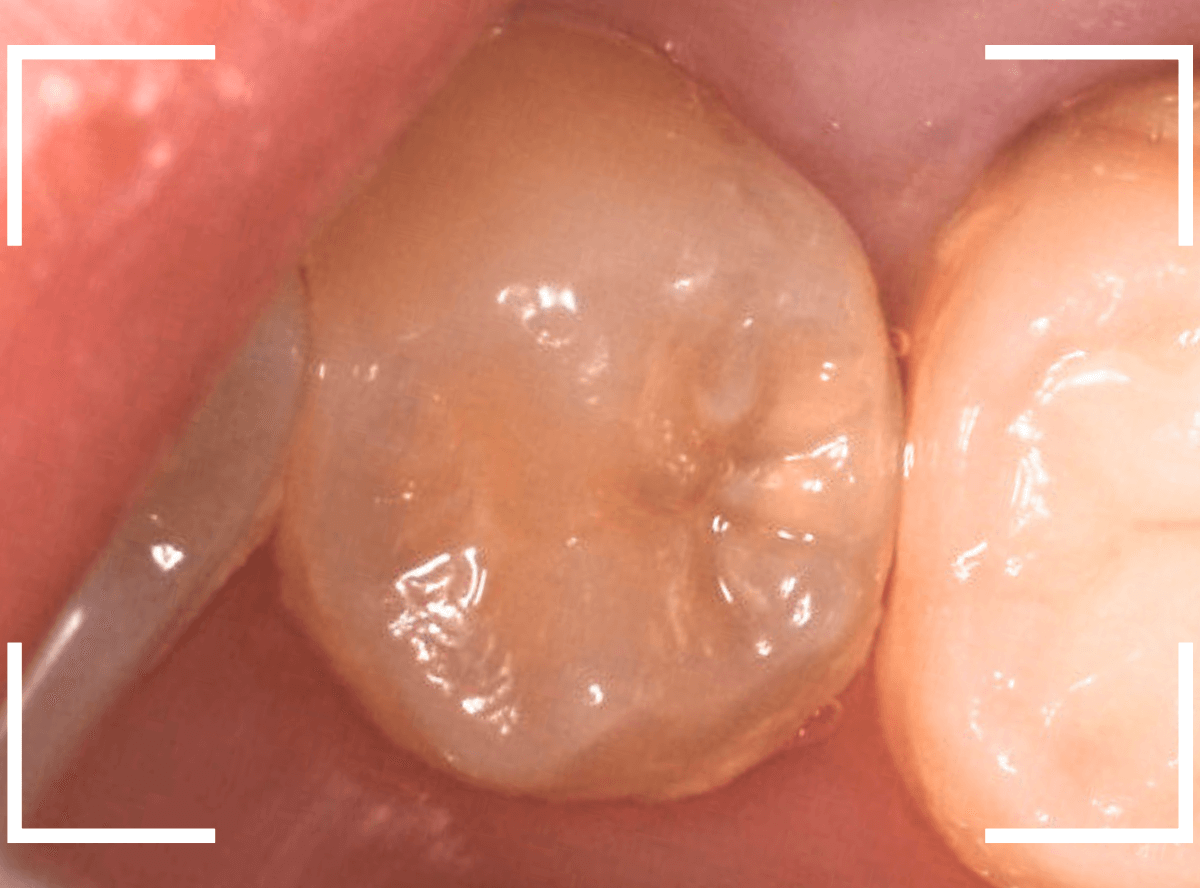

Case.1 奥歯のスキマが大きな虫歯!

他の歯の治療目的で来院された患者さんです。

全体検査の際、ちょっとこの歯、アヤシイなと思いましたが、確証はありませんでした。

(この写真で改めて見ると、かなりアヤシイと思いました)

レントゲン写真で確認すると、かなり大きな虫歯でした。